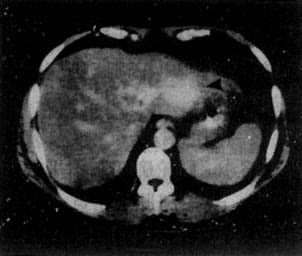

图4-3-5 原发性肝癌

CT增强扫描,肝右叶有一较大圆形低密度肿块(↓),其边缘

部可见多个较密度的强化结节,其强化程度不如正常肝,中

心部仍为未强化的低密度区